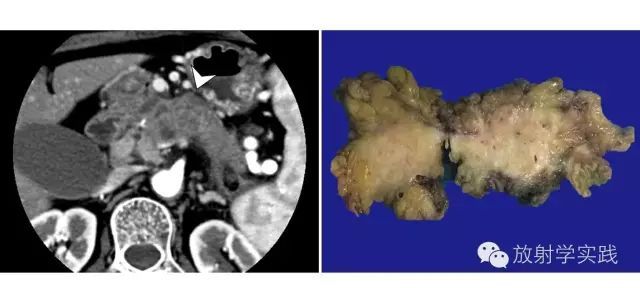

对PNEN认识的深入,发现囊变的不少,以胃泌素瘤和无功能肿瘤多见,胰岛素瘤相对少见[7]。胰岛素瘤通常体积较小,动脉期强化显著,而非功性PNEN的强化方式与细胞增殖指数Ki-67阳性指数及肿瘤是否侵犯血管有关,G1期肿瘤较G2、G3期肿瘤在动脉期强化更显著[14];体积较大的肿瘤可因中央区域坏死、囊变或退变、玻璃样变性而呈现周边“花环样”显著强化、中央无强化的表现,这是与其它囊实性肿块的重要鉴别点(图4)。

图4 胰腺神经内分泌肿瘤(PNEP)。a)胰腺实质期CT增强图像,显示肿块明显强化(箭);b)另一层面示病灶可见典型的花环状强化。